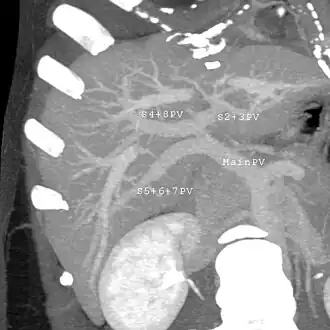

With the recent advances of noninvasive imaging, living liver donors usually have to undergo imaging examinations for liver anatomy to decide if the anatomy is feasible for donation. The evaluation is usually performed by multidetector row computed tomography (MDCT) and magnetic resonance imaging (MRI). MDCT is good in vascular anatomy and volumetry. MRI is used for biliary tree anatomy. Donors with very unusual vascular anatomy, which makes them unsuitable for donation, could be screened out to avoid unnecessary operations.

-

MDCT image. Arterial anatomy contraindicated for liver donation -

MDCT image. Portal venous anatomy contraindicated for liver donation -

MDCT image. 3D image created by MDCT can clearly visualize the liver, measure the liver volume, and plan the dissection plane to facilitate the liver transplantation procedure. -

Phase contrast CT image. Contrast is perfusing the right liver but not the left due to a left portal vein thrombus.